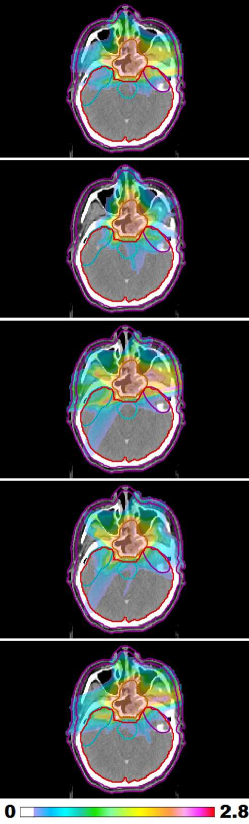

Figure 1: LABEL:sub@prt_allFracs and LABEL:sub@lng_allFracs Fraction-variant treatment plans for each of five fractions for cases “PRT” and “LNG”. The PTV receives a uniform dose of 888 Gy (approximately) at each fraction for case “PRT” and 9.6 Gy (approximately) for case “LNG”. LABEL:sub@hnk_allFracs Dose colormaps for fractions 1, 7, 13, 19, and 25 for case “H&N”. The PTV receives a uniform dose of 2.2 Gy (approximately) throughout the treatment course.

Figure 1LABEL:sub@hnk_allFracs shows the dose distributions for a selection of five of the 30 treatment fractions for the FV head and neck plan. Despite the variation in dose distributions, the PTV is covered uniformly at each fraction. Each voxel in the PTV receives a dose of approximately 66/30=2.266302.266/30=2.2 Gy per fraction. The FV BOO algorithm selected only 6.366.366.36 beams per fraction, on average. As in all cases, the algorithm did not select the same set of beam angles for any two fractions. A total of 81 distinct beam firing positions were utilized, as illustrated in figure 8LABEL:sub@hnk_beams_allFracs.

Figure 9 shows the total dose distribution, summed over all 303030 fractions, for the FV plan (top row) as well as a 7-beam FI plan (middle row) and a 13-beam FI plan (bottom row). Corresponding dose-volume histograms are shown in figure 10. Compared with the 7-beam FI plan, the FV plan achieves dosimetric improvements for the cochleas (bilateral), chiasm, brainstem, parotids, and orbits. Mean dose was reduced by 10.2 Gy (cochleas), 3.4 Gy (chiasm), 1.2 Gy (brainstem), and 1.0 Gy (orbits). Max dose was reduced by 10.0 Gy (cochleas), 6.7 Gy (orbits), 5.7 Gy (brainstem), 4.7 Gy (parotids), 1.6 Gy (brain), and 1.4 Gy (pharynx). The dosimetric quality of the FV plan is comparable to that of the 13-beam FI plan.

Figure 9: Visualizing the dose distribution (summed over all 30 fractions) for FV plan with average of 6.36 beams per fraction (top row) as well as a 7-beam FI plan (middle row) and a 13-beam FI plan (bottom row). Dose below 5 Gy is not shown.